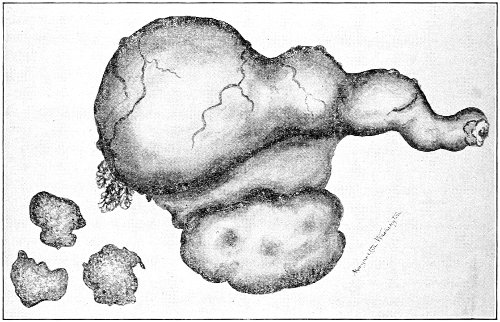

Suppuration of the vulvo-vaginal gland is accompanied by marked swelling and peripheral edema. The swelling may extend to the anus, and is of characteristic shape (Fig. 17). The pain is always severe. Fluctuation is first apparent on the inner surface of the labium majus. If the condition is not treated, one or more fistulous openings appear below the orifice of the duct, and the pus is discharged. The condition then becomes chronic. The fistulous openings persist. Acute inflammation disappears from the gland, leaving it in a condition of hypertrophic induration. A thin, milky or greenish, purulent fluid may be pressed out of the duct or the fistulous openings. Infection from this discharge may be communicated to man, or may ascend the genital 40 tract, producing inflammation of the endometrium or of the Fallopian tubes.

Fig. 17.—Abscess of right vulvo-vaginal gland.

In abscess of the vulvo-vaginal gland a free incision should immediately be made into the labium at the junction of the skin and the mucous membrane. The interior should be wiped out with pure carbolic acid and the cavity packed with gauze. If the disease is first seen in the chronic stage, after the abscess has evacuated itself, the only method of cure is to excise, with curved scissors, the whole of the indurated gland, the duct, and the fistulous tracts. The wound may be left open and packed, or it may be closed immediately with buried catgut sutures.